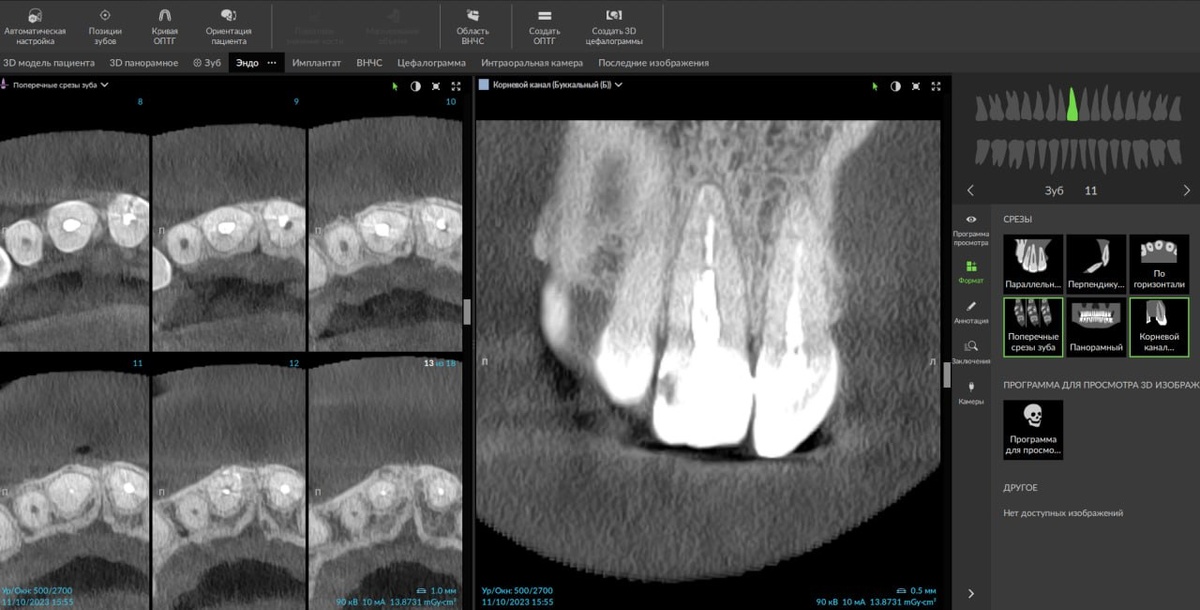

От хода основного канала отходит дополнительный канал под 90° - латеральное ответвление:

Рис. 1

Может выходить на вестибулярную (1 и 3 рис.) или палатинальную поверхность корня, что создает сложность обнаружения при помощи классической 2D-рентгенографии:

Рис. 3

В данном кейсе, работая в DTX Studio Clinic, использовали вкладку ENDO, которая позволяет вращать плоскость реформата вокруг оси канала зуба